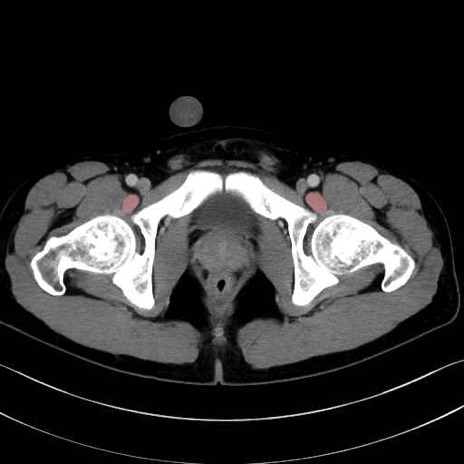

4. 深層外旋六筋(股関節の深部)

梨状筋 (Piriformis)

内閉鎖筋 (Obturator internus)